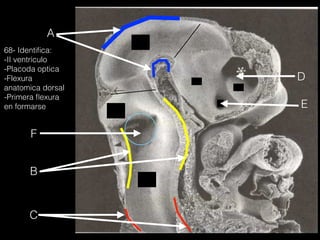

68- Identifica:

-II ventrículo

-Placoda optica

-Flexura

anatomica dorsal

-Primera flexura

en formarse

A

B

D

C

F

I

H

E

G